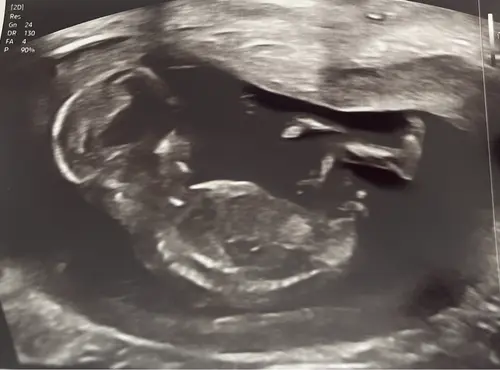

Iemand enig idee? 🫶🏼